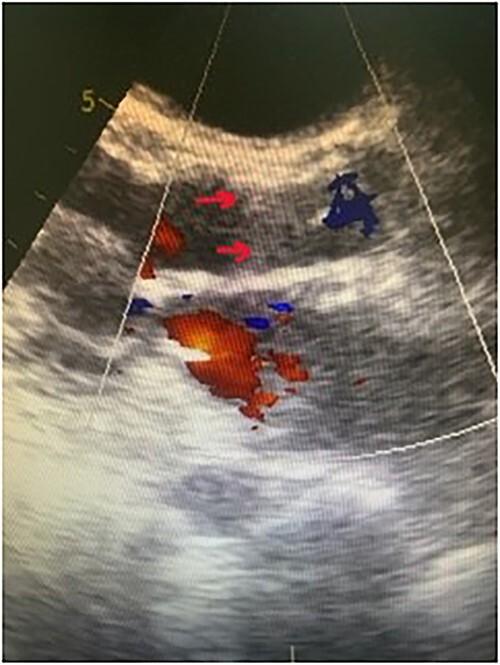

De novo aortic regurgitation (AR) presents a great challenge following left ventricular assist device (LVAD) implantation and requires valve replacement in some cases. Patients with LVAD are frequently those who underwent multiple previous sternotomies or suffer from multiple comorbidities. Thus, they are at high surgical risk for further sternotomy. Transcatheter aortic valve implantation (TAVI) previously approved for treatment of severe aortic stenosis is also used for this category of patients. Here, we report the case of a young female patient supported with heart mate II LVAD who presented with severe de novo AR. The patient was successfully treated with TAVI using Myval trancatheter heart valve (THV) in our center. To our knowledge, our patient is the first to be treated with such type of valve using TAVI procedure in LVAD supported patients.

植入左心室辅助装置(LVAD)后,新发主动脉瓣反流(AR)带来了巨大挑战,在某些情况下需要进行瓣膜置换。LVAD患者通常是那些之前接受过多次胸骨切开术或患有多种合并症的人。因此,他们接受进一步胸骨切开术的手术风险很高。先前被批准用于治疗严重主动脉瓣狭窄的经导管主动脉瓣植入术(TAVI)也用于这类患者。在此,我们报告一例接受HeartMate II LVAD支持的年轻女性患者,该患者出现严重新发AR。在我们中心,该患者使用Myval经导管心脏瓣膜(THV)通过TAVI成功治疗。据我们所知,我们的患者是首例在LVAD支持的患者中使用此类瓣膜通过TAVI手术进行治疗的。